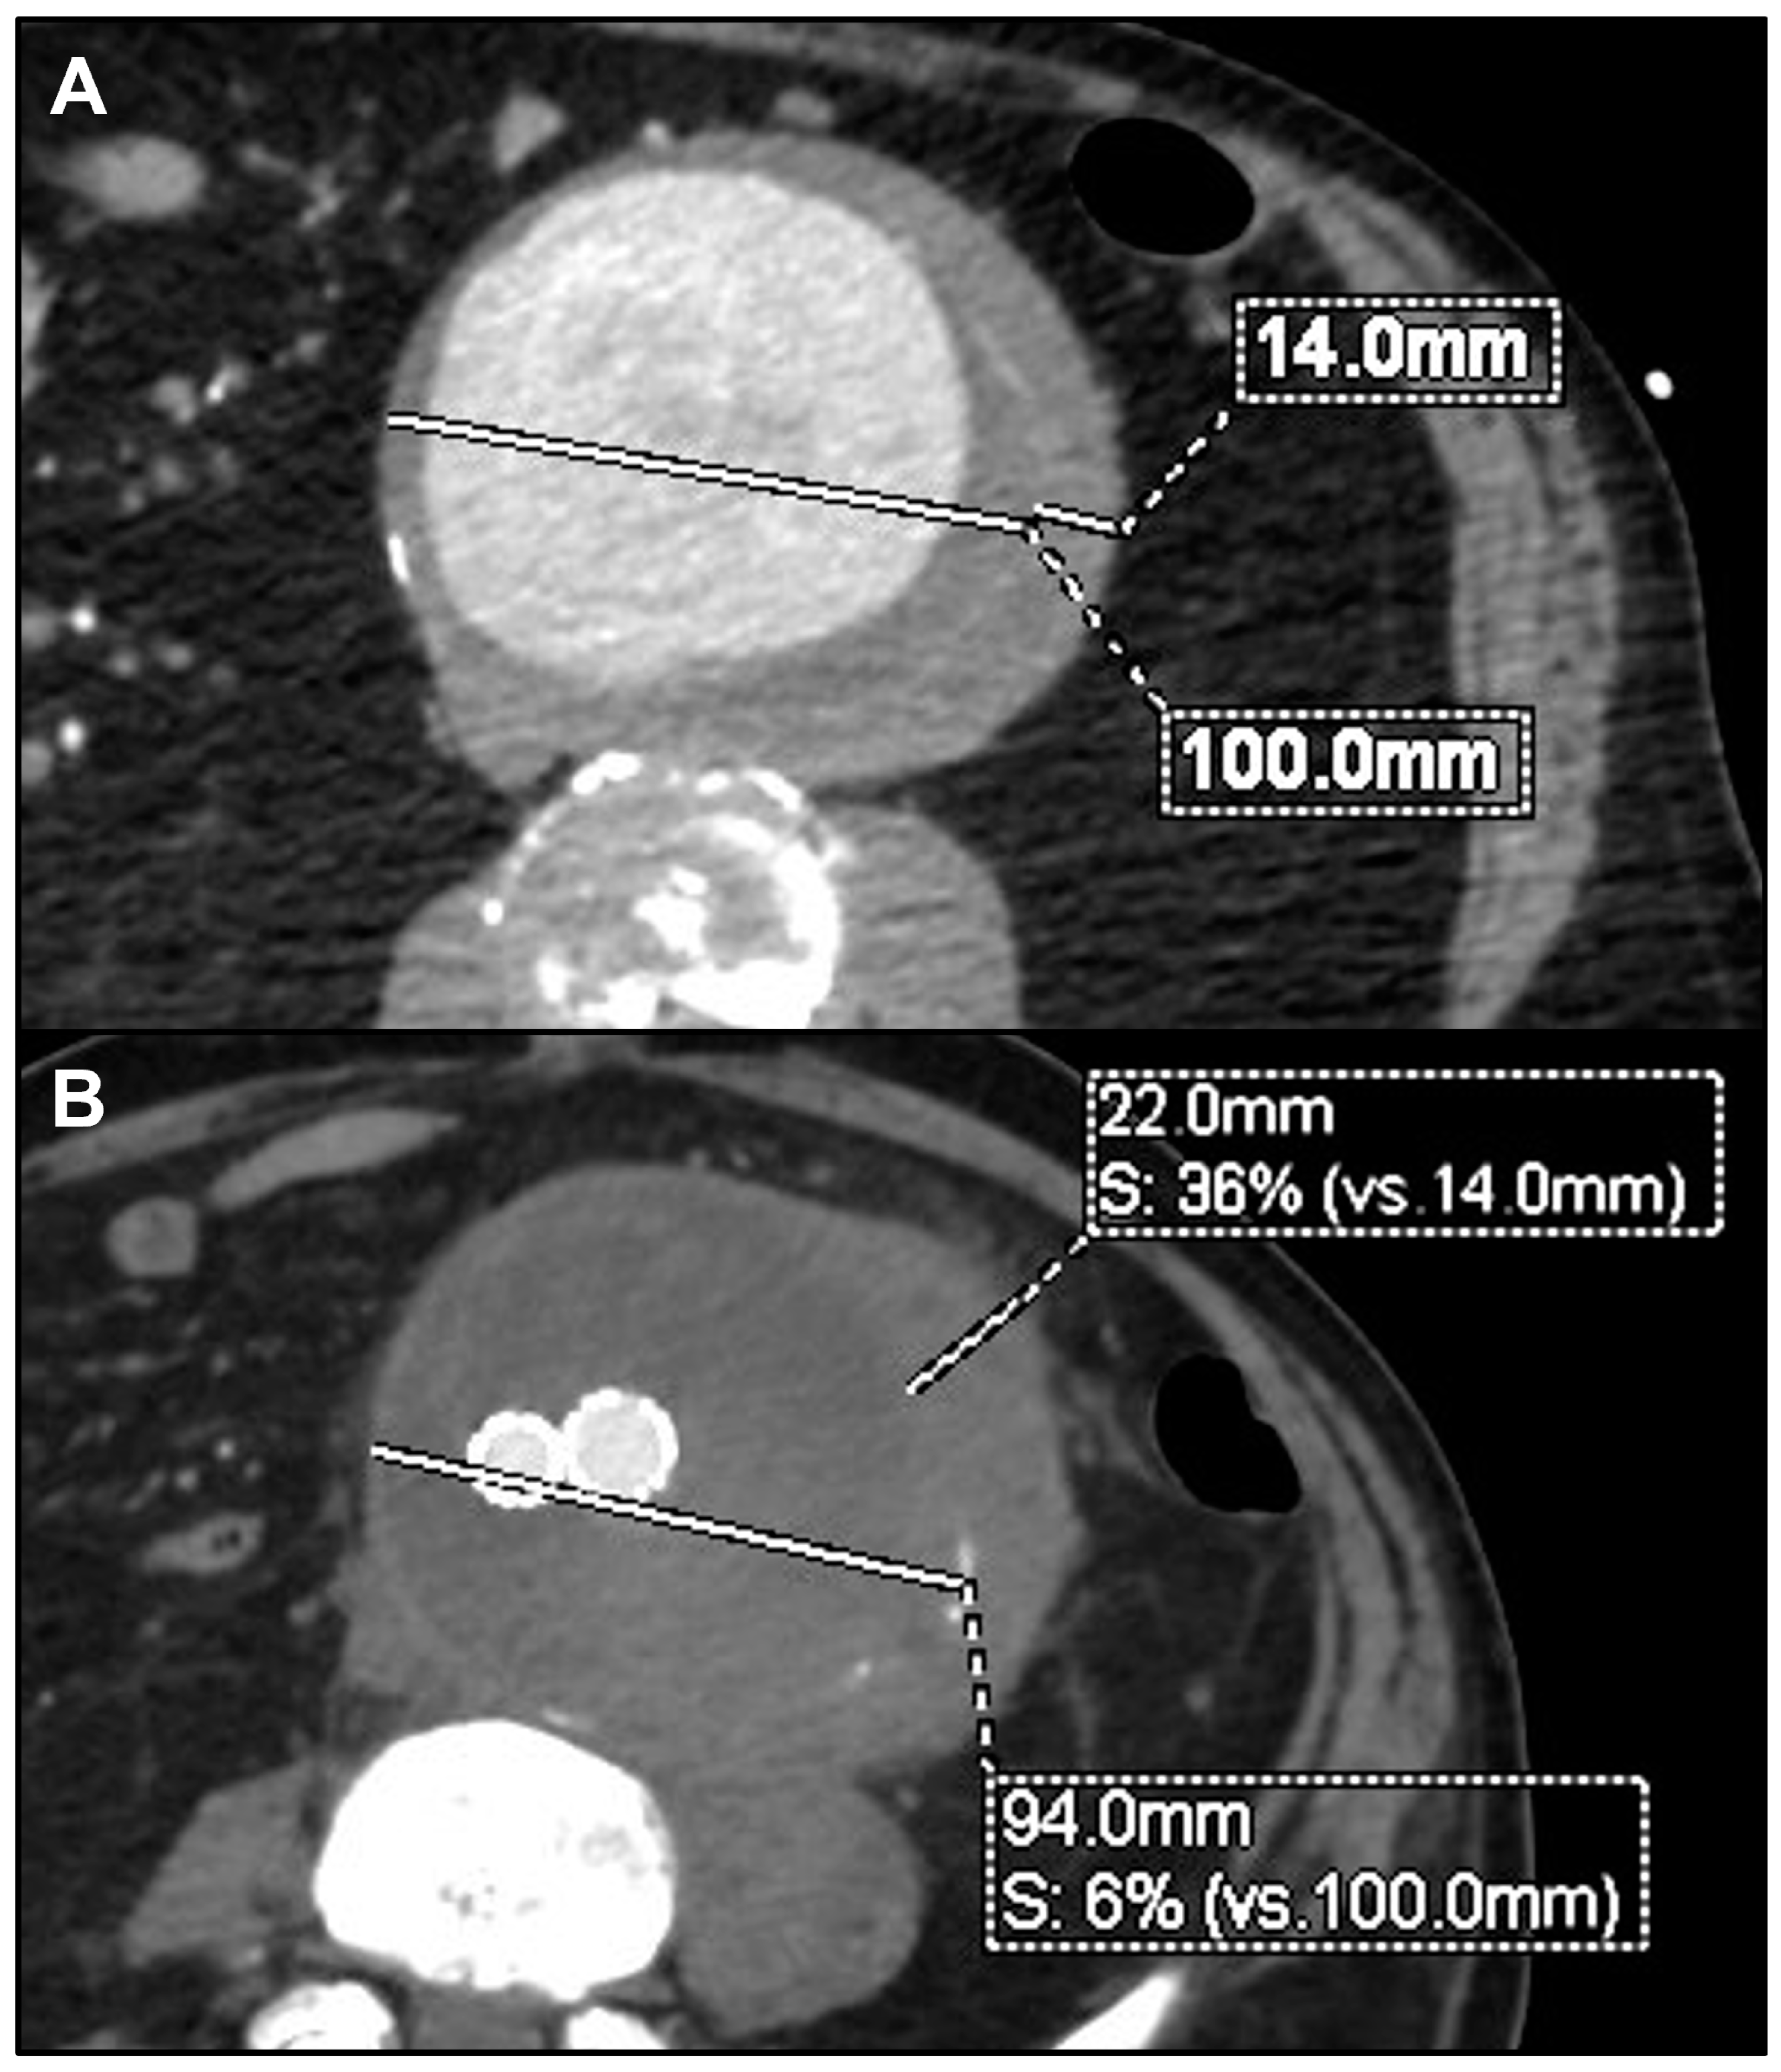

During the mean follow-up of 31.6 ± 23.1 months (range 1–71), no further death or major adverse event was registered among the remaining 13 alive patients. Re-interventions were performed in three cases (20%). One patient originally treated with TEVAR required, 1 month later, a proximal thoracic extension and left subclavian artery coverage and embolization for disease progression. Another patient treated with BEVAR underwent, after 1 year, TEVAR for a new-onset isolated non-contiguous aortic arch saccular lesion. The third patient, previously treated with a straight abdominal tube graft, required a distal extension with a bifurcated stent graft, after 5 months, for distal disease progression and rupture of the aortic bifurcation. The same patient presented an aneurysmal degeneration of the proximal aortic neck, which is currently under surveillance after 55 months from the index procedure (Figure 1). Another patient, treated with EVAR for symptomatic rapidly growing infrarenal aneurysm, showed after 3 months a significant growth of the peri-aortic inflammatory tissue, without an indication for a re-intervention so far (Figure 2). Except these, no other patient reported any signs of recurrences or endograft infection during the follow-up. No case of open conversion was registered. Aneurysm shrinkage > 5 mm or stability was noted in 10 of the 13 patients who survived the early period after repair. Preoperative and postoperative details for each patient are summarized in Table 2.

Figure 2. Preoperative computed tomography angiography (CTA) of symptomatic rapidly growing 100 mm infrarenal aneurysm (A) and 3-month postoperative CTA showing aneurysm’s shrinkage but significant growth of the peri-aortic inflammatory tissue (B).